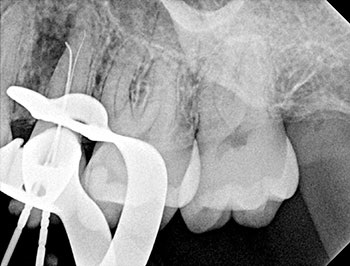

Fig. 4: Recall CBCT.

The patient returned in three months, when resolution of symptoms, healing of the deep probing defect and bone regeneration were confirmed. The tooth was obturated, and a foundational restoration was placed before the rubber dam was removed. Fourteen years of follow-up confirmed long-term periradicular health. The amount of appreciation and gratitude that this patient expressed reminds us that each individual tooth demands our best efforts.